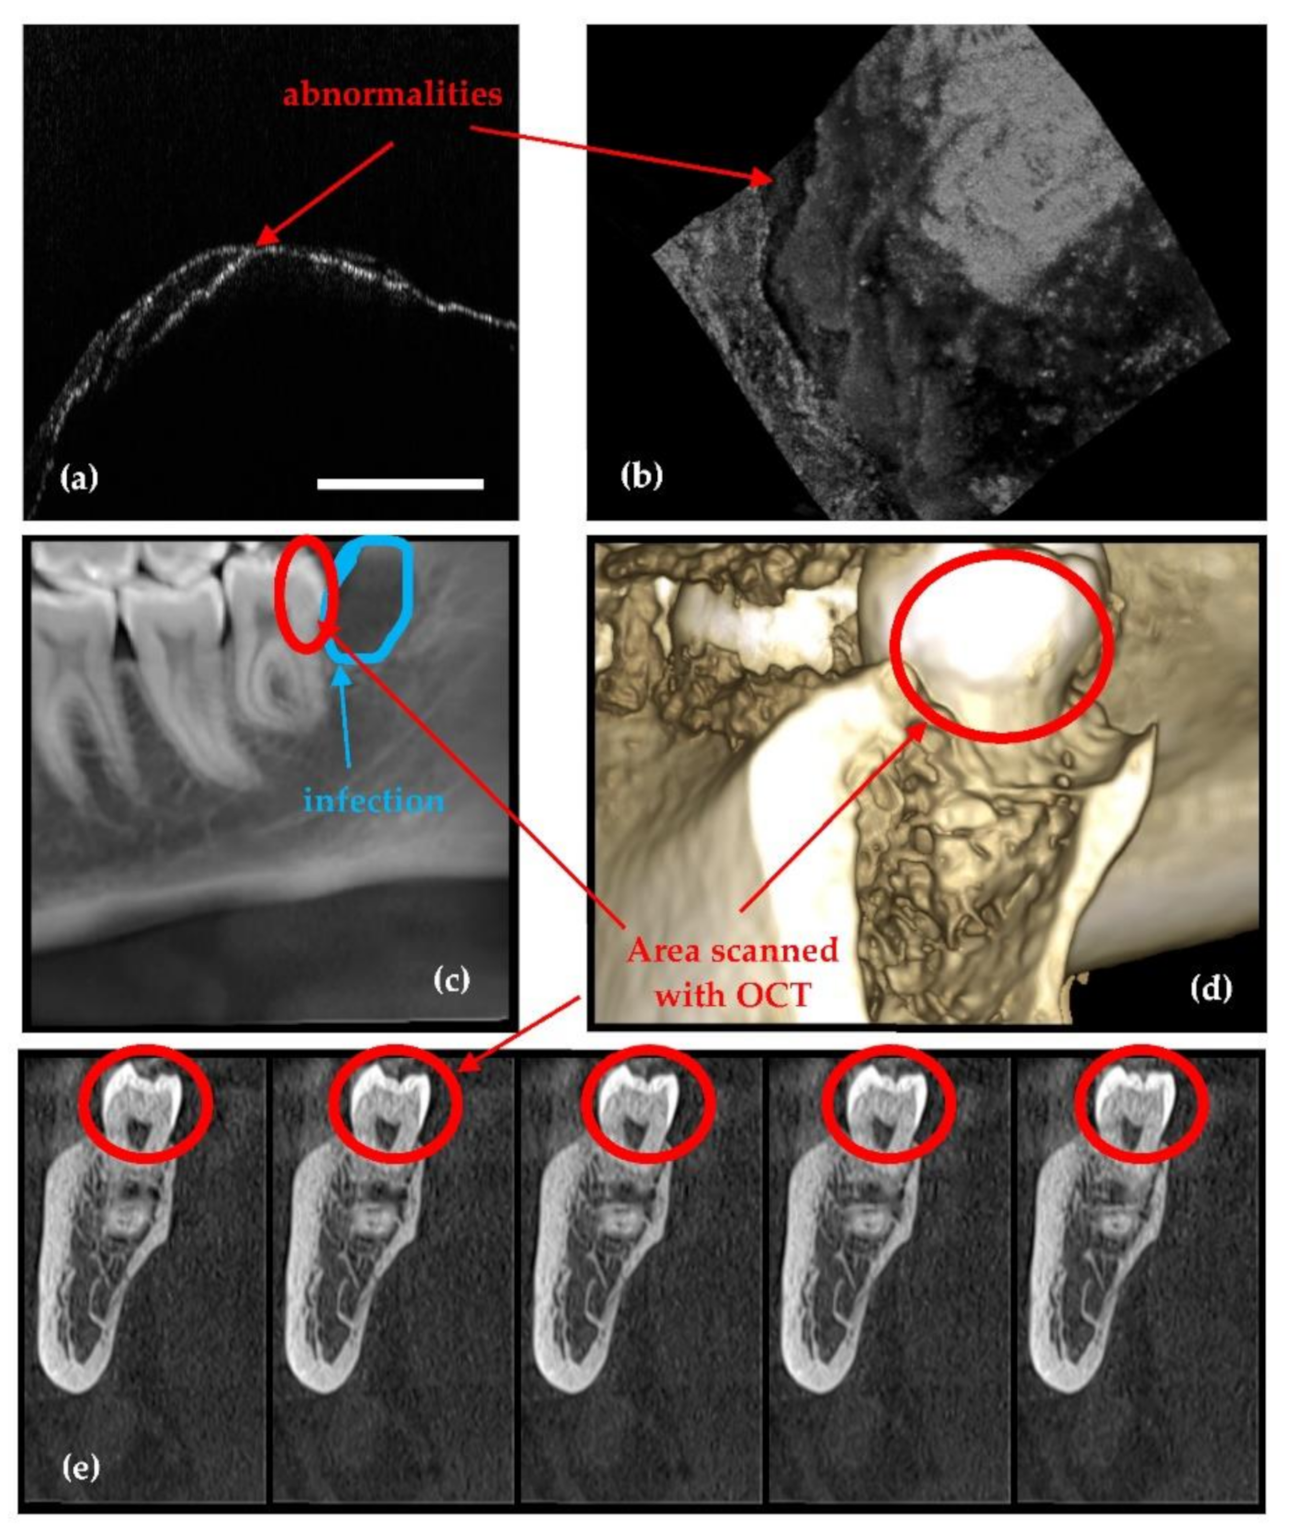

2.4. The Concept of X-ray Imaging Optimization Using OCT

2.5. OCT versus Radiography

- Because it is using IR laser radiation, OCT does not penetrate metals, although studies of their roughness can be made [46] and, as shown in Figure 4, OCT can provide images near dental crowns, while 3D CBCT for example cannot achieve such images. Also, we have demonstrated that OCT can replace the gold standard of SEM in the study of metallic fractures [47,48]. Therefore, a subject of future work in our groups refers to OCT studies of metallic parts included in the oral cavity, for example dental implants.